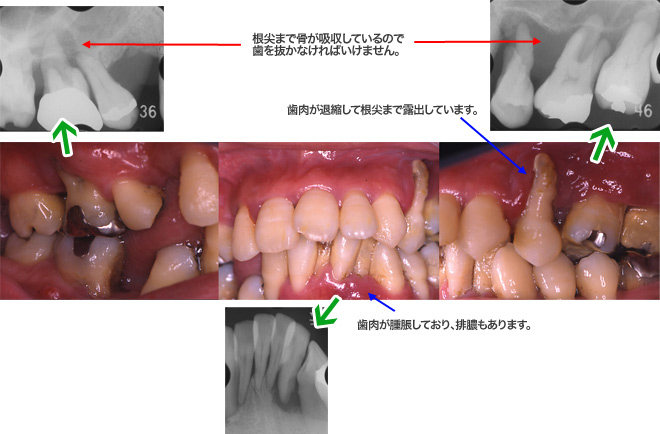

症例3:特殊なタイプの歯周病

- 早期発症型歯周炎(侵襲性歯周炎)

- 若年者に発症するタイプの歯周病です。歯周病が重症な場合が多いので要注意です。早期の徹底した歯周病治療が歯を保存するためにも必要です。

- 患者

- 29歳、男性

- 主訴

- 歯肉の腫脹、および咀嚼障害

- 現病歴

- 10代の頃から、歯肉腫脹を自覚していたが、特に歯周病の治療を受けることなく放置。20代になり疲れたときや体調が悪い時に歯肉が腫脹し,痛みを感じることが多くなった。歯が自然脱離し、物が食べにくくなったため、治療を希望して来院した。

- 全身疾患

- 特に無し

- 診断

- 早期発症型歯周炎